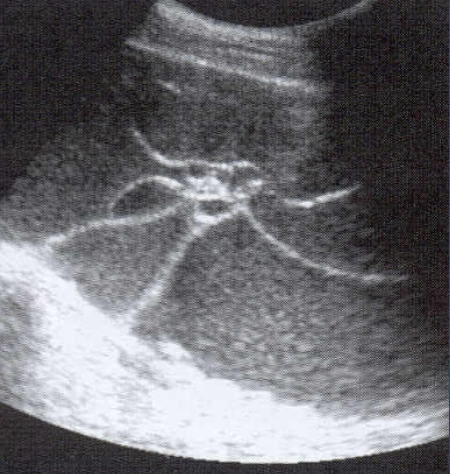

Fibroids U/S appearance:

Depends on number and size

Uterine enlargement

Hypo- to hyper- echoic

Heterogenous texture

Distorted uterine contour

May displace endometrium

Calcification causes shadowing

Trandsabdominally → able to appreciate large fibroids

Transvaginally → small fibroids